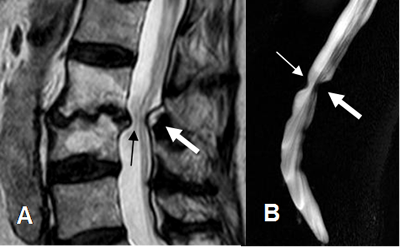

Fig 108. Regresión de hernia.

A y B: RM sagital en GE. Hernia paramediana derecha. En un control 2 años después, ha disminuido la compresión del saco dural.

Fig 109. Regresión de hernia.

A y B: RM axial en T2. Hernia paramediana derecha. En un control posterior, ha disminuido el tamaño y la compresión de las raíces.

Fig 110. Regresión de hernia.

A y B: RM sagital en T2. Hernia mediana en L3-L4, que después de 7 meses, muestra disminución de su tamaño y menor compresión del saco dural. Cambios degenerativos en las placas terminales de L3-L4 y

L4-L5 y artefactos sobre el cuerpo de L4, ocasionados por materia de fijación posterior. (Puntas de flecha).